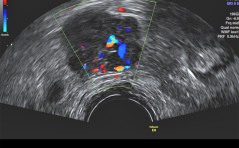

Der suspekte Adnexbefund in der Praxis PDF Dokument

Sonoquiz

Woran denken Sie? PDF Dokument

Auflösung Sonoquiz

Tiefsitzender Sinus marginalis placentae PDF Dokument